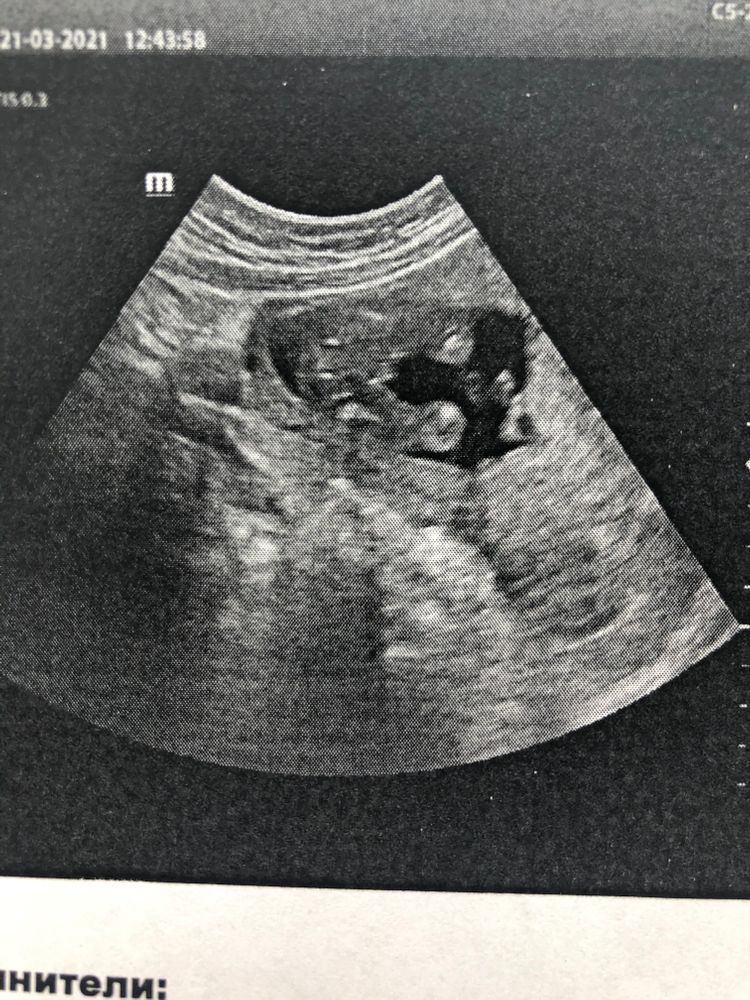

УЗИ, КТГ, доплерДевочки, привет! У мужа во вторник день рождения. Хотели лопнуть шарик с полом, вчера специально сходили на узи. Но нашего терпения хватило только выйти из клиники и сесть в машину😂 И мы развернули бумажку с полом) 90 % мальчик. Хочу закрасить кружочек но пока только 90%. А вдруг ошибка. Хоть мне и кажется, что писюн не увидеть ещё можно и ошибиться, что это девочка, а вот если он потарчивает, то ошибка минимальна... Посмотрите?)

Ну у вас стопроцентный писюн😏у нас девочка и между ног было видно кофейное зернышко, тоже на сроке 16 недель ходила

Да где тут сомнения могут быть? Парень! 💙

Вот мой в 18 недель был такой.

Вот у моей девы в 16 нед. Нам говорили 80 процентов девочка. Точно показали бантик в 20 нед)))

Думаю, у вас мальчик.